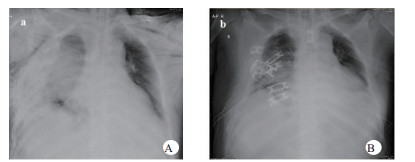

1 资料与方法患者,男,63岁,因“车祸致呼吸困难1 d”入院。既往体健。患者于2019年9月30日翻车致胸部挤压性创伤,伤后出现极度呼吸困难,送至当地医院,测血压80/50 mmHg(1 mmHg=0.133 kPa),胸部CT提示右侧血气胸,给予输血补液、去甲肾上腺素维持血压,经鼻气管插管呼吸机辅助通气,放置胸腔闭式引流管2根。因循环及氧合维持困难,10月1日转至徐州医科大学附属医院,收入EICU。入院查体:T 36.7℃,P 152次/min,R 14次/min(机械通气支持),BP 110/67 mmHg[去甲肾上腺素0.5 μg/kg·min)维持]。处于镇静状态,双侧瞳孔等大等圆,直径约2.0 mm,对光反射未引出;全身多处皮肤软组织擦挫伤,颈部及前胸、上肢广泛皮下气肿,右侧胸壁显著塌陷,反常呼吸,听诊双肺呼吸音低;心率快、心律齐、心音不遥远;腹部无异常体征;2根胸腔闭式引流管引流通畅。入院当天CT检查显示:双侧肋骨骨折伴右侧胸壁塌陷,两肺挫伤、创伤性湿肺,右肺撕裂伤,右侧液气胸,双侧胸壁广泛皮下气肿(图 1:A, B, C);未见颅内出血及腹部器官损伤。入室后0.5 h血气分析:pH 7.18,PCO2 57.5 mmHg,PO2 67.1 mmHg,Lac 4.4 mmol/L,氧合指数67.1 mmHg,APACHE Ⅱ评分27分。治疗上予镇痛镇静、保护性肺通气策略、保温、预防感染等治疗,效果不佳,连枷胸,皮下气肿范围不断扩大,氧合指数持续<100 mmHg。于10月2日气管切开后行V-V ECMO治疗(右股静脉—右颈静脉);因右侧血胸、胸引量24 h达1 000 mL,血红蛋白下降,凝血功能显著异常,存在创伤性凝血病,采取无肝素抗凝ECMO技术,提高血流速(4.6 L / min),气流速(5 L / min),FiO2 100%;给予成分输血,监测ACT及APTT。ECMO转机1h后去甲肾上腺素停用,复查血气分析PO2 105 mmHg。此后,患者氧合和血流动力学逐步改善,创伤性凝血病已纠正,于10月7日在无肝素V-V ECMO支持下行“胸骨骨折切开复位钢板内固定术+右侧3、4、5前肋肋骨骨折环抱器内固定+右侧5、6、7、8后肋肋骨骨折环抱器内固定术+两侧胸腔闭式引流术”。术中见第5肋骨前端骨折向下外移位,3、4肋骨多段骨折,胸壁前上方完全塌陷,肺脏直接外露,胸腔内布满血凝块,术中取出血凝块共约1 000 mL。术后氧分压上升至400 mmHg,术后复查床边胸片,肺部影像学较前改善(图 2 A, B),继续无肝素V-V ECMO治疗1 d后,于10月8日开始肝素抗凝,维持ACT在160 s~180 s,APTT在40 s~50 s,肝素化期间无出血并发症发生。10月11日行自主氧合试验通过,予以撤机。10月12日复查胸部CT两肺复张满意(图 3 A, B),开始间断停用呼吸机并床边康复训练。10月28日撤离呼吸机,气切处高流量吸氧。11月15日拔除气切管。11月18日康复出院,无明显并发症发生。

| 图 1 A胸部CT纵隔窗(右侧胸壁塌陷);B胸部CT肺窗(广泛皮下积气,肺挫伤);C肋骨三维重建(多根多处肋骨骨折)。 |